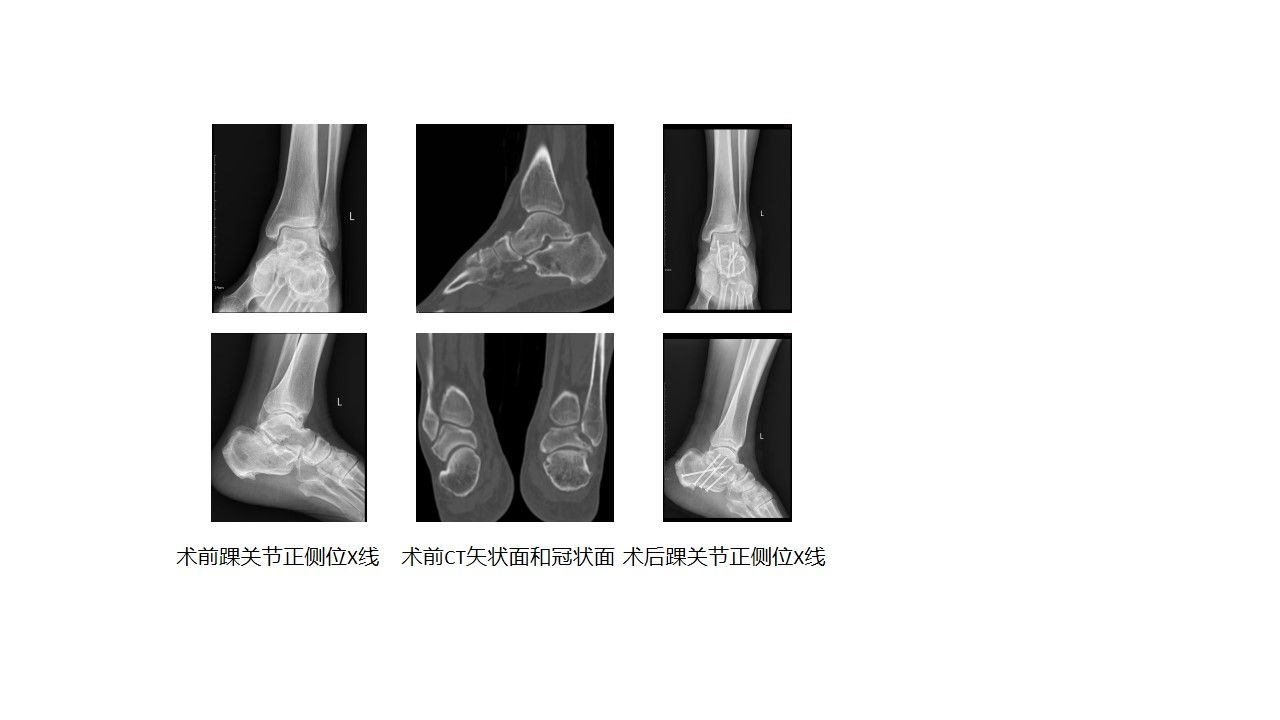

今年 60 岁的张先生,15 年前意外致左侧跟骨骨折,保守治疗后好转,却陷入长期疼痛困境。日常行走、站立受明显影响,长期接受药物镇痛、物理康复等保守治疗,疼痛仍反复加重,生活质量严重下降,夜间睡眠受扰。为求根治,张先生经多方打听慕名前往我院运动医学科就诊。接诊的宋启春副研究员通过细致问诊、全面体格检查及 CT 等影像学评估,明确诊断为 “距下关节关节炎”,且关节内已出现明显软骨损伤与骨质增生,保守治疗已无法有效控制病情。

手术在时志斌主任医师全程指导下有序开展,宋启春副研究员主刀,梁佳林博士、陈清莆进修医生密切配合。术中,宋启春副研究员通过关节镜精准定位病变区域,彻底清除受损软骨与增生骨质,精细修整距骨、跟骨关节面以确保融合面贴合度,随后采用 4 根生物相容性螺钉,以 “三角固定” 原理将距下关节稳固融合,整个手术衔接流畅,历时约 1 小时顺利完成。术后首日,张先生便反馈左踝关节疼痛明显缓解,可在医护指导下进行轻度踝关节活动,还告诉医务人员 “我终于能睡个好觉了”;术后一周康复护理后,其切口愈合良好,生命体征平稳,目前已转入康复治疗阶段,逐步恢复踝关节负重功能。